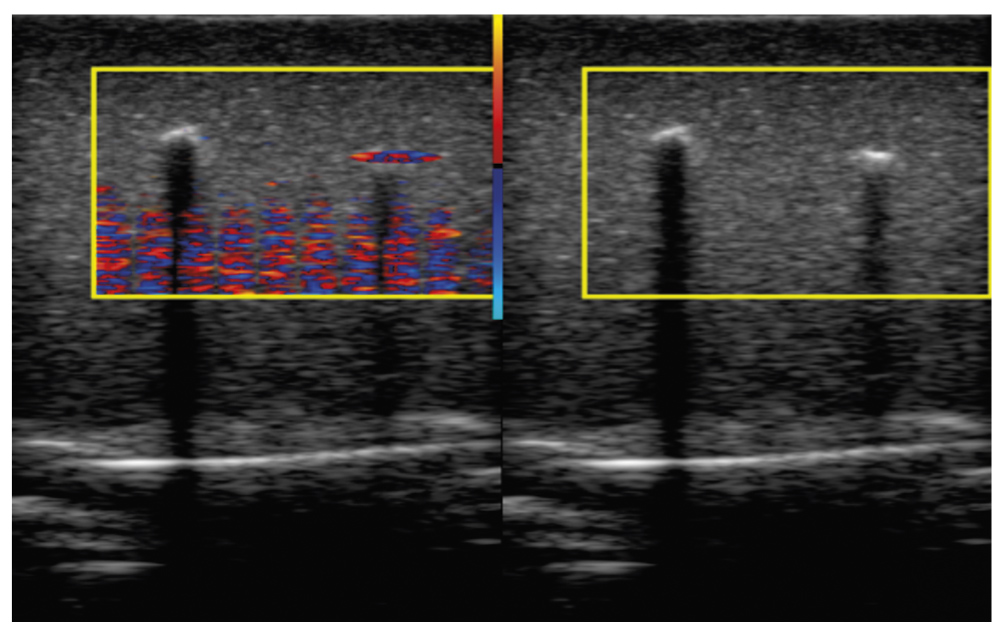

Examples of “slow” time signals, which determine the Doppler pattern, are shown in Fig. 5. Typical graphs of signals from different areas are shown here:

- The area of the blood-mimicking fluid flow in the Doppler phantom channel of the Gammex 1430 LE Mini-Doppler Flow System (real and imaginary parts of the signal change in quadrature, which is typical for moving objects; Fig. 5a).

- The area of soft tissues in the absence of motion (after filtering the signal from the tissues, only the noise remains; Fig. 5b).

- The observation area of the twinkling artifact on a steel wire (a random signal is observed, which differs from the noise in Fig. 5b by greater dispersion; Fig. 5c).

- The observation area of the twinkling artifact on a smooth object (the signal shows a periodicity resulted from micro-oscillations of the observed object; Fig. 5d).

Fig. 5. Examples of visualization of radio frequency signals using the TwinklingDatasetDisplay program: a - fluid flow in the Gammex phantom; b - soft tissue area in the absence of movement; с - signal of a flickering artifact on a rough object; d - signal of a flickering artifact on a smooth object. In the left column, complex signals are presented as a parametric line in polar coordinates (the real part is displayed along the abscissa axis, the imaginary part along the ordinate axis). The right column shows the dependence on "slow" time within the burst.